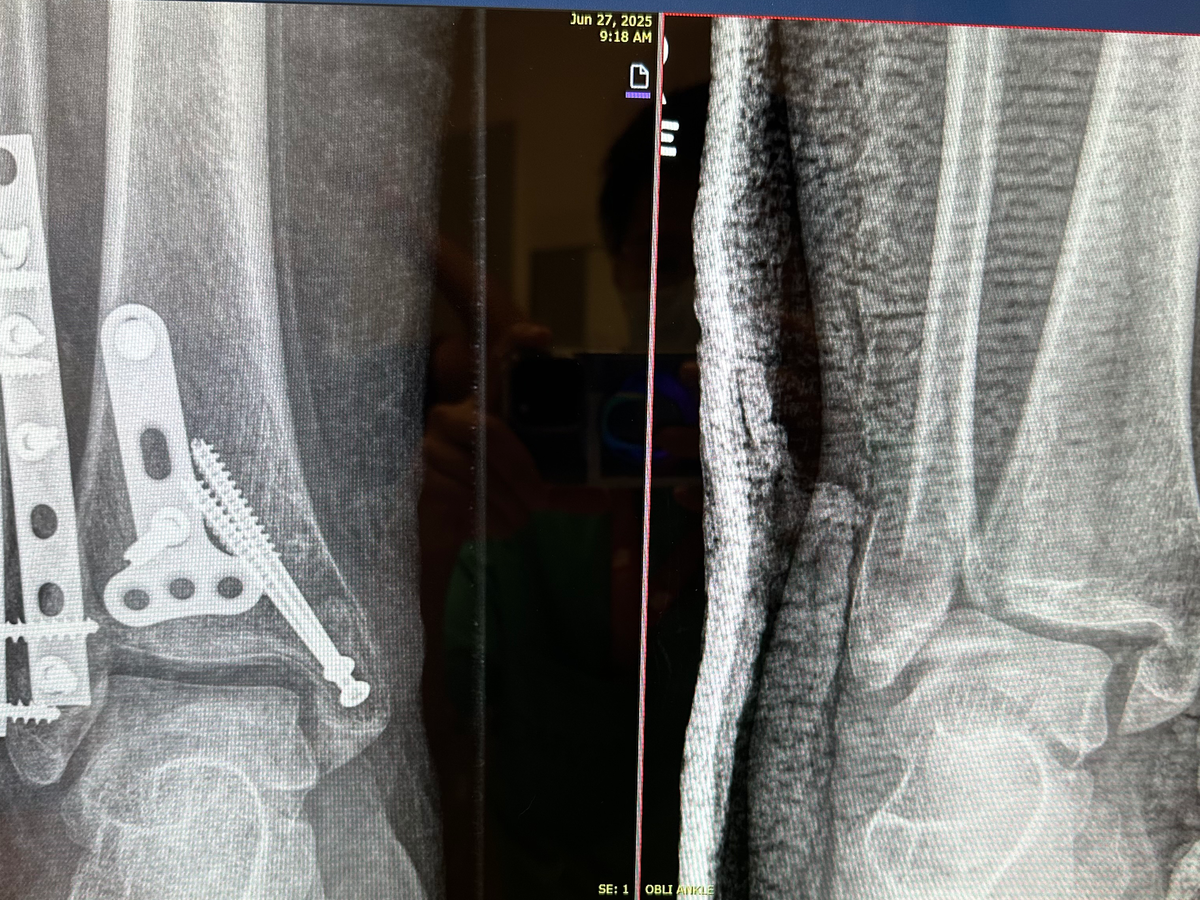

On April 25th, I had an accident stepping down stairs from a venue in San Francisco that resulted in a trimalleolar fracture on my right ankle. That means I broke my ankle in the critical three points that it connects to the foot and leg; basically, I broke it in the worst way possible.

Currently, I am being seen by SCVM without insurance and have been applying for financial assistance programs through the hospital as well as applying for disability (waiting on approval). The team at Valley Medical has been great to me but are limited in what to provide/expect for my needed future follow-up appointments as I have been unable to pay for most services provided so far. I am still going to require follow-up appointments with X-ray imaging, as well as physical therapy so that I can get back to walking and return to work and a somewhat normal life.